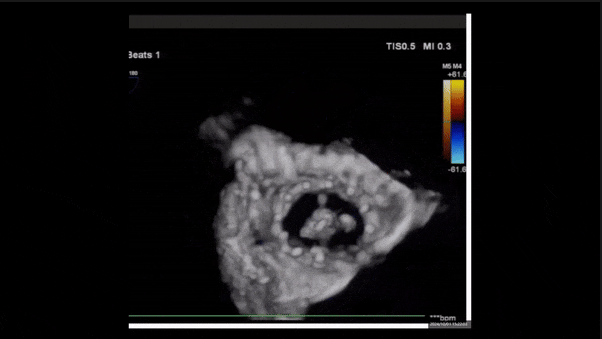

1、3D TEE顯示雙房及右室擴大,右室中段直徑40mm,右室FCA 52%。三尖瓣環TAPSE 22mm,三尖瓣環左右徑49mm,三尖瓣隔葉長度16mm,前葉長度21mm,后葉長度34mm,三尖瓣前隔gap 11mm,后隔gap 5.6mm,AP gap 12mm,診斷極重度功能性三尖瓣返流(Type I型三尖瓣:Torrential FTR 5+)。

術后三維超聲

術后即刻經食道超聲可見,三尖瓣假體瓣膜位置合適,牛心包瓣葉運動狀態良好,開閉正常,瓣周及瓣葉對合緣處未見明顯返流,心電圖及心包狀態較術前無明顯變化。